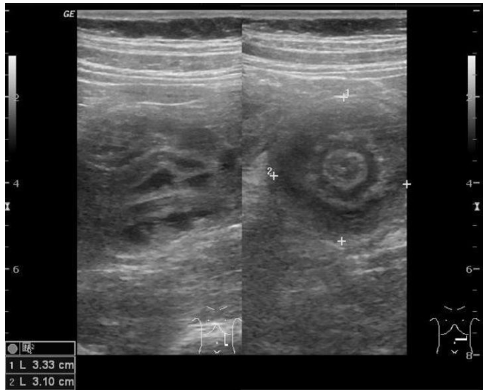

Target sign on USG Abdomen is suggestive of _____.

Buddha sign/Halo sign is suggestive of _____